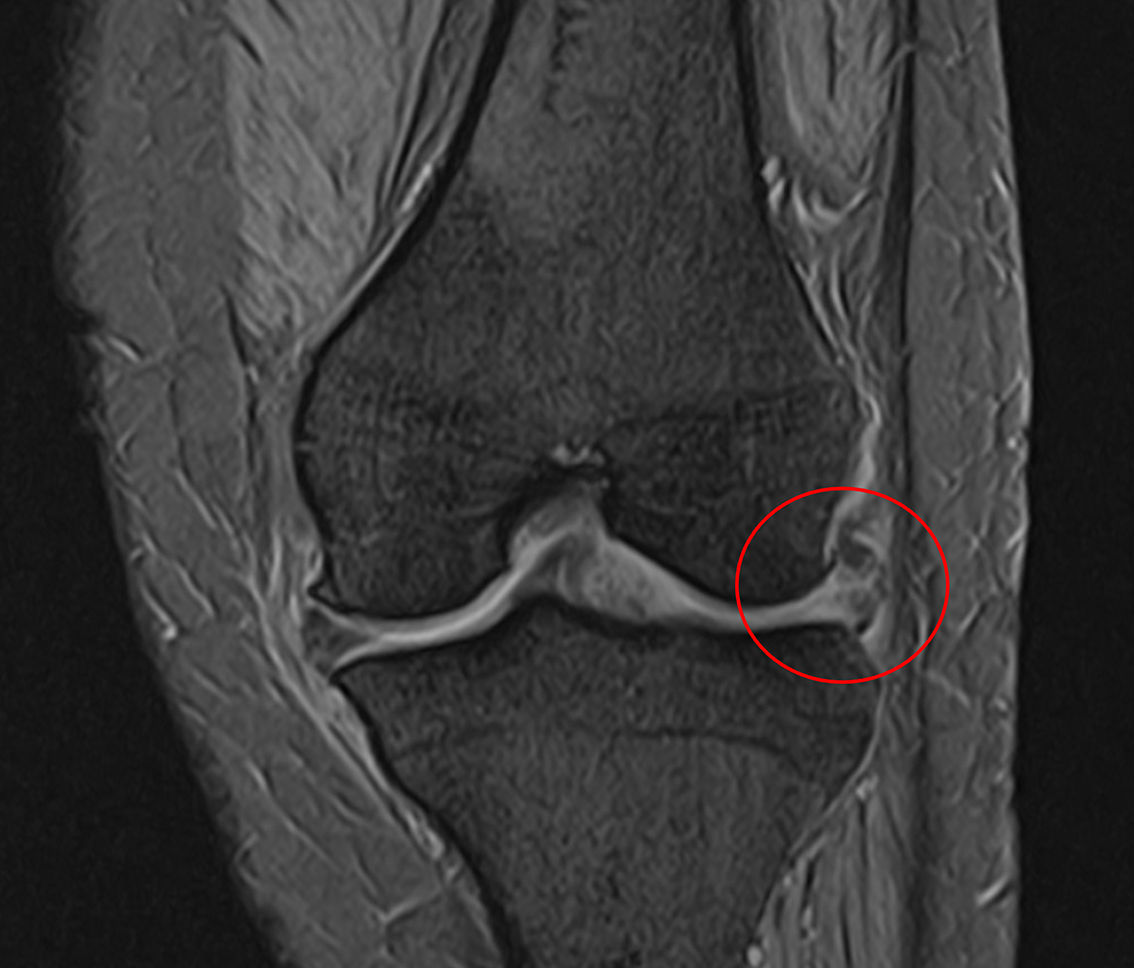

MRI画像でも炎症は治まり、半月板の再生や軟骨が生えてきていることを確認。

半月板の炎症や腫大軽快。

膝周囲の炎症(白っぽさ)が軽快している